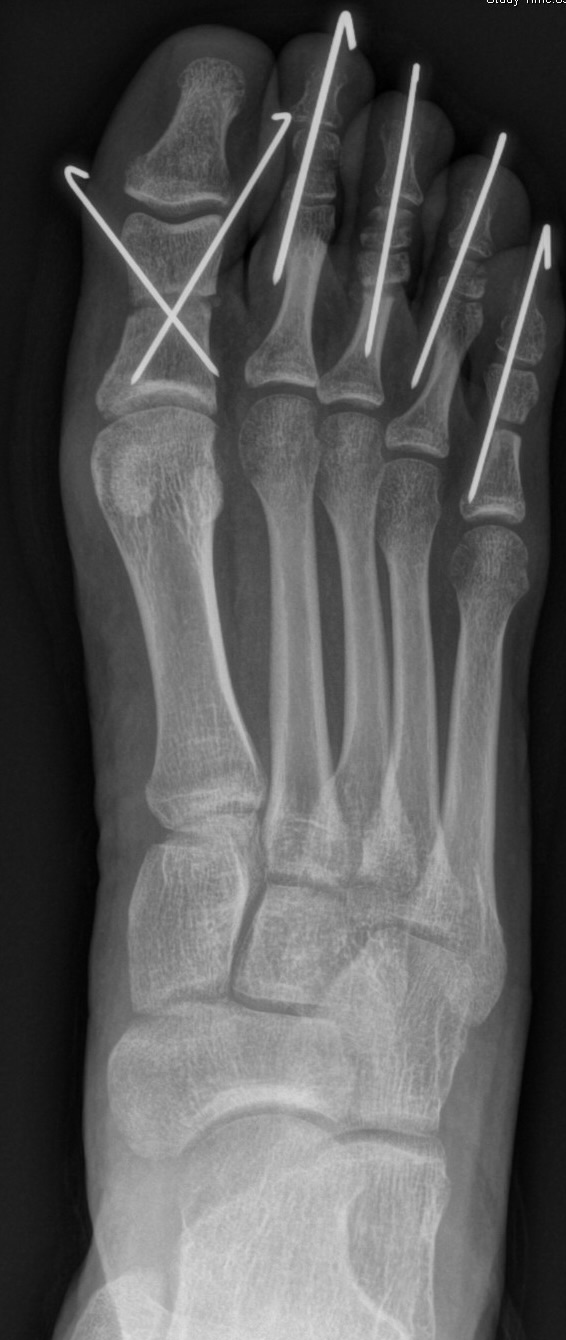

Die Chevron Osteotomie 1 ist ohne Komplikationen am wachsenden Skelett durchführbar. Das Metatarsale I besitzt distal keine Wachstumsfuge, die geschädigt werden könnte. Die „französische Methode nach Marc Elkaim“ eignet sich für Kinder ganz besonders (Abb. 28).

Abb. 28 a-g: Radiologischer Verlauf einer Chevronosteotomie nach dem Verfahren von M. Elkaim mit prä- (a-c drei unterschiedliche Ansichten) und intraoperativen Röntgenbildern in zwei Ansichten (d-e) sowie postoperativ zwei Ansichten (f-g).

Sie wird über eine eigene Tapetechnik fixiert und kann bei einem erhöhten Intermetatarsale-Winkel alternativ zur Scarf-Osteotomie durchgeführt werden. Nachteile der Methode sind eine deutliche Verkürzung durch die Fräse sowie eine starke Plantarisierung des Metatarsale I Köpfchens. Um die Verkürzung zu vermeiden, wird verlängernd in Richtung des Metatarsale II Köpfchens (nicht wie offen in Richtung Metatarsale IV Köpfchen) osteotomiert. Gleiches gilt für die starke Plantarisierung, die durch den Knochenverlust der Fräse entsteht. Die Korrektur eines kindlichen oder jugendlichen Hallux valgus ist mit der Methode ansonsten suffizient durchführbar. Wird verkürzt, muss ausreichend plantarisiert werden, um eine Transfer-Destabilisierung MT II-IV zu vermeiden.

Die MICA-Technik sollte bei geschlossenen Fugen mit einem weitem intermetatarsale Winkel durchgeführt werden. Die dafür typische Verschraubung der Osteotomie kann bei geschlossenen Fugen ohne Probleme erfolgen. Diese Osteotomie kann gut mit einer Akin- und den beschriebenen Kleinzehen-Osteotomien kombiniert werden.